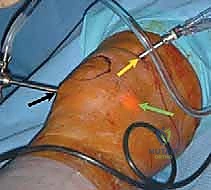

- المنظار التشخيصي (Diagnostic Arthroscopy): في بعض الحالات، يكون المنظار الجراحي هو الوسيلة الأدق للتشخيص النهائي وتقييم مدى صلابة الغضروف المحيط بالآفة، حيث يتم إدخال كاميرا دقيقة إلى داخل المفصل لتقييم الوضع على الطبيعة قبل أو أثناء اتخاذ قرار العلاج.

يُصنف هذا الإجراء تحت فئة "تحفيز نخاع العظم". عندما يكون هناك عيب غضروفي كامل السمك (أي أن العظم مكشوف تماماً)، يقوم الجراح باستخدام أداة دقيقة تشبه المخرز (Awl) لعمل ثقوب صغيرة في هذا العظم المكشوف.

هذه الثقوب تخترق الطبقة العظمية الصلبة (Subchondral bone plate) وتصل إلى نخاع العظم الغني بالأوعية الدموية. نتيجة لذلك، تخرج من هذه الثقوب قطرات من الدم والدهون تحتوي على مكونات سحرية: الخلايا الجذعية الميزنكيومية (Mesenchymal Stem Cells - MSCs) وعوامل النمو القوية.

3. تبني أحدث التقنيات (مناظير 4K): لا يعتمد الدكتور هطيف على الطرق التقليدية فحسب، بل يستخدم أحدث أجهزة المناظير بتقنية 4K، والتي توفر رؤية مكبرة وفائقة الوضوح لأدق تفاصيل الغضروف، مما يسمح بإجراء تنظيف دقيق وعمل ثقوب مثالية دون الإضرار بالأنسجة السليمة المحيطة.